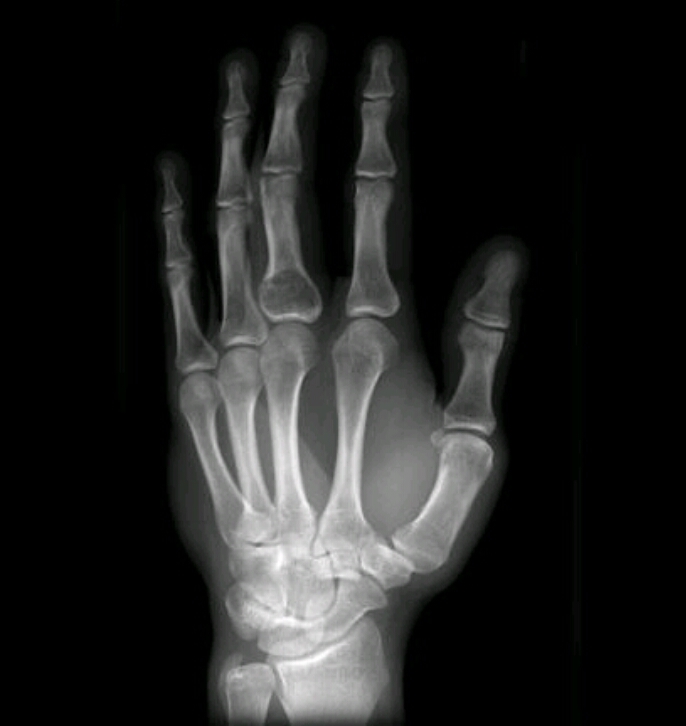

Findings? Diagnosis?

Geographic, central, oval radiolucency with long axis parallel to bone

POSSIBLE FALLEN FRAGMENT SIGN, OPEN GROWTH PLATES

Solitary bone cyst